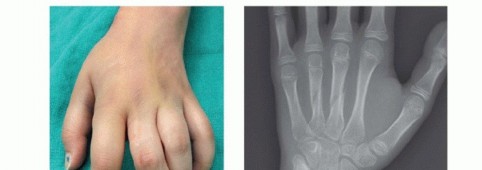

Clinical & Radiographic Imaging Archive